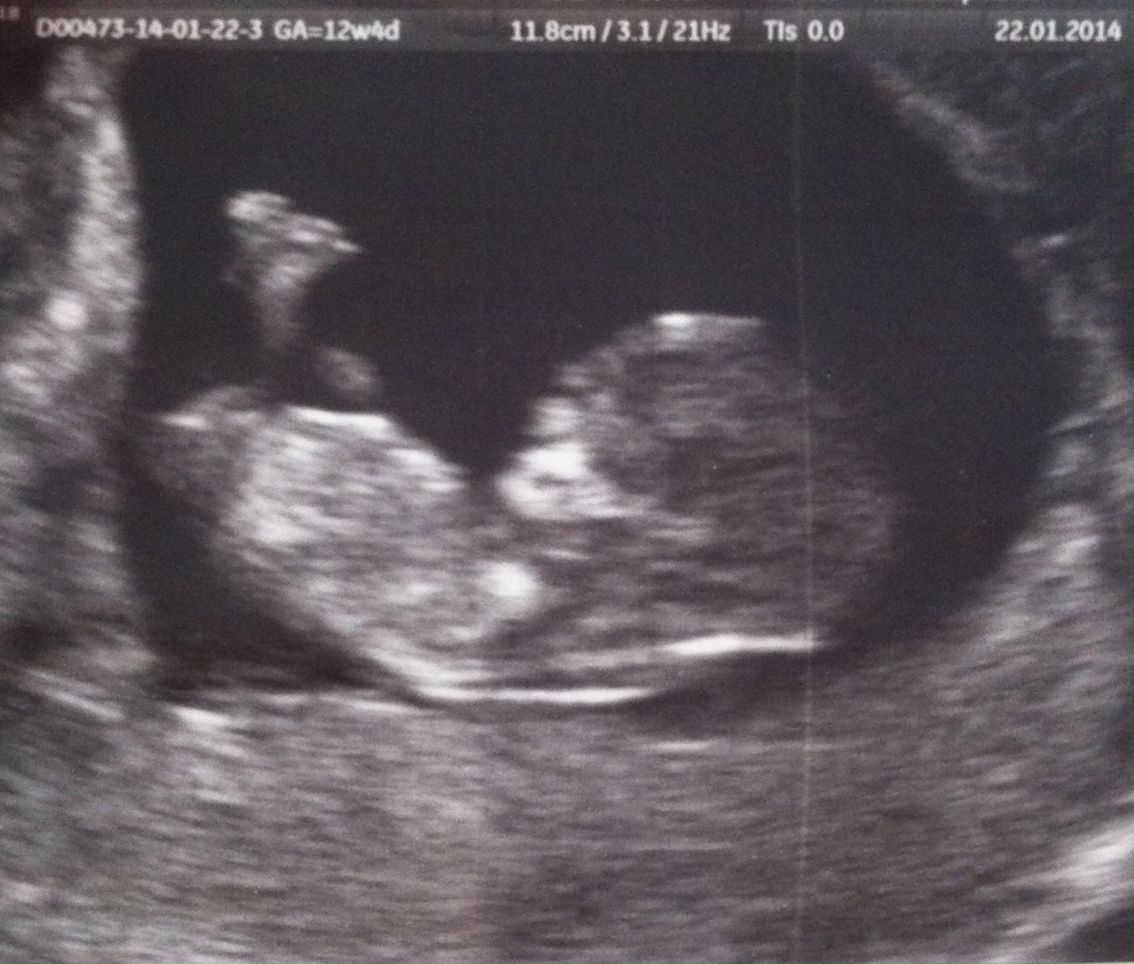

Please guess! Dr. says girl, what say you?? :) UPDATED: New U/S pics, can you see a nub?

So this is a tricky one IMO. The baby is not lying competely sideways, more like in an angle with bottom half pointing up and leaning to the right, if that makes sense...

Doctor (a specialist in maternal-fetal medicine) said probably girl. I know it's still early (don't mind the GA 12w4d, was corrected to 11W), but I would love your opinions!! Have become completely nubsessed... :worry: